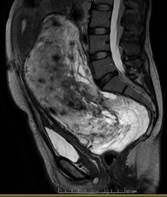

Posteriormente se realizó una resonancia magnética de abdomen y pelvis, en la que se observó una masa pélvica extraperitoneal con extensión abdominal, de 230mm x 183mm x 106mm de tamaño, muy bien delimitada, provocando desplazamiento severo de recto, de útero y anexos, y de vejiga. Dicha tumoración se mostró hipointensa en T1 e hiperintensa en T2 (imágenes 1 2 y 3).

En cuanto a la imagenología, la resonancia magnética permite una mejor planificación quirúrgica gracias a su alta precisión para identificar invasión de estructuras adyacentes1. Es frecuente encontrar una masa iso o hipointensa en T1 e hiperintensa en T2 gracias a su gran contenido en matriz y de agua, y es posible encontrar un patrón característico en espiral o remolino, manifestando su componente fibrovascular13. Otros estudios de utilidad debatida son la ecografía abdominal, en la que se halla una imagen hipoecoica o quística y vascularización periférica al Doppler7, y la tomografía computada, identificando una masa hipodensa y heterogénea de márgenes bien definidos y su característica forma arremolinada ante la administración de contraste7.